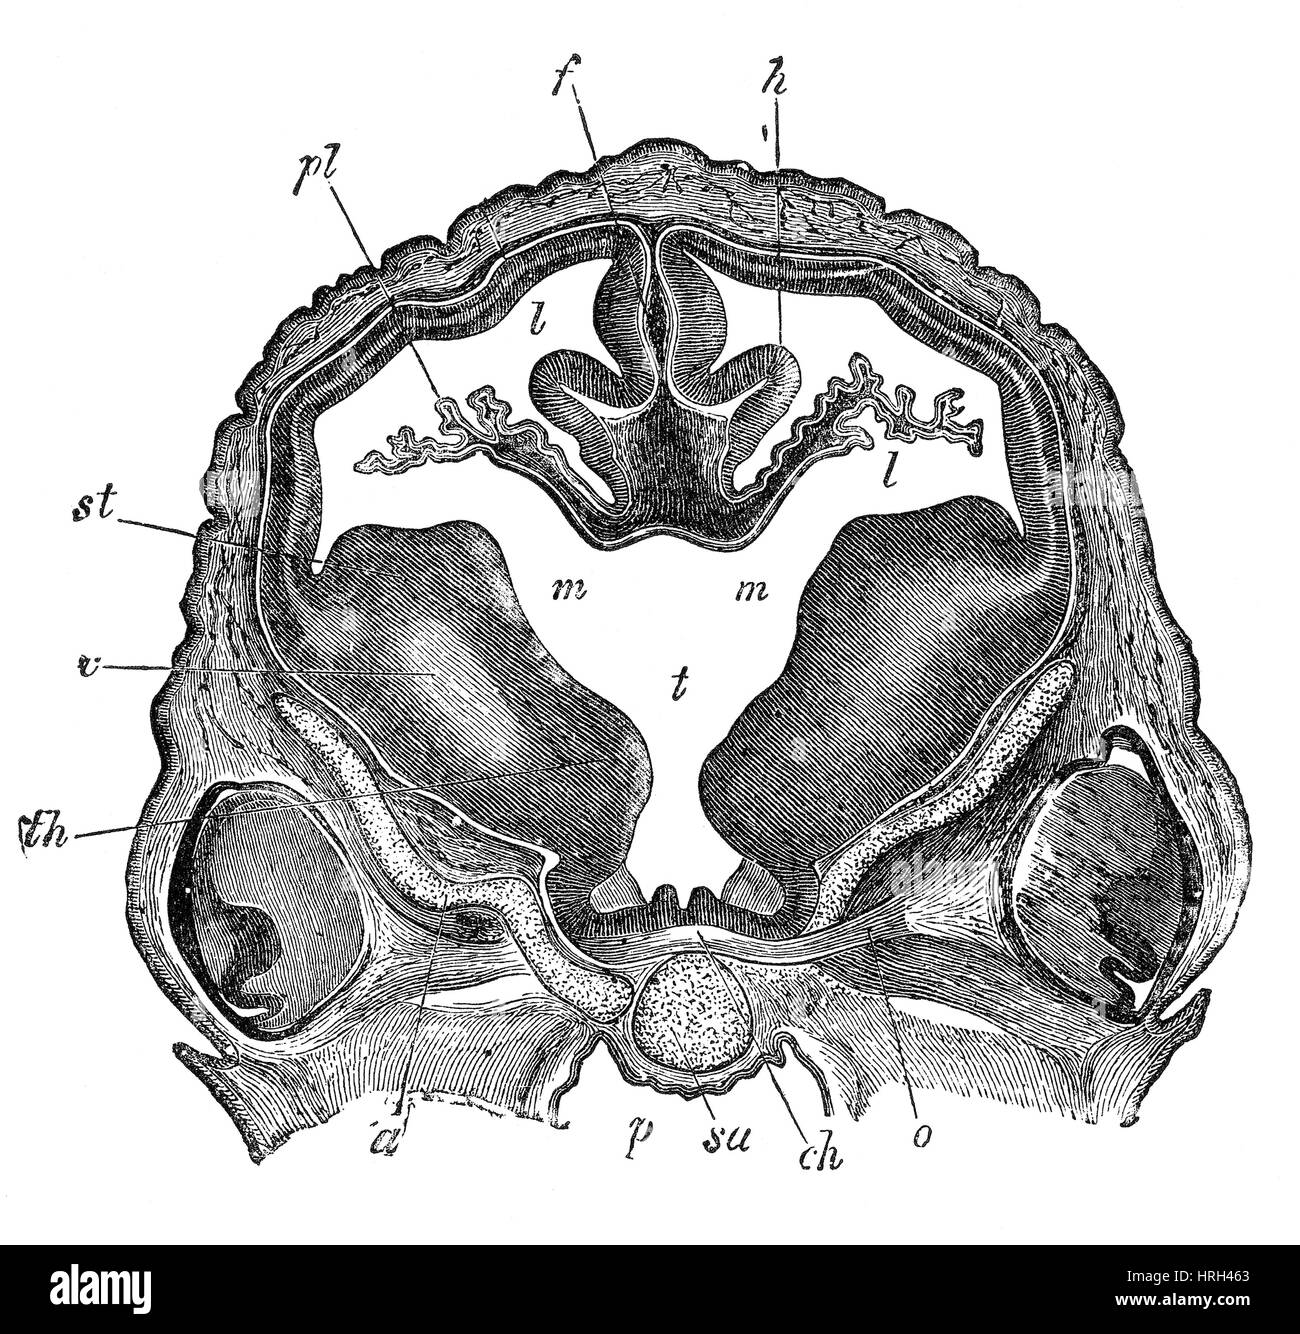

RF3CN8WHP–Illustration des vergrößerten lateralen und dritten Ventrikels des Gehirns (Hydrozephalus), hervorgerufen durch einen Hirntumor, der den Aquädukt des Gehirns komprimiert.

RMG155NW–Verbesserte Darstellung der sagittalen Abschnitt der dritten und vierten Ventrikel des Gehirns Farbe. Die Ventrikel enthalten Liquor cerebrospinalis, die das Gehirn dämpft. Dies ist eine historische Darstellung aus den 1890er Jahren. (Abb. BS4911)